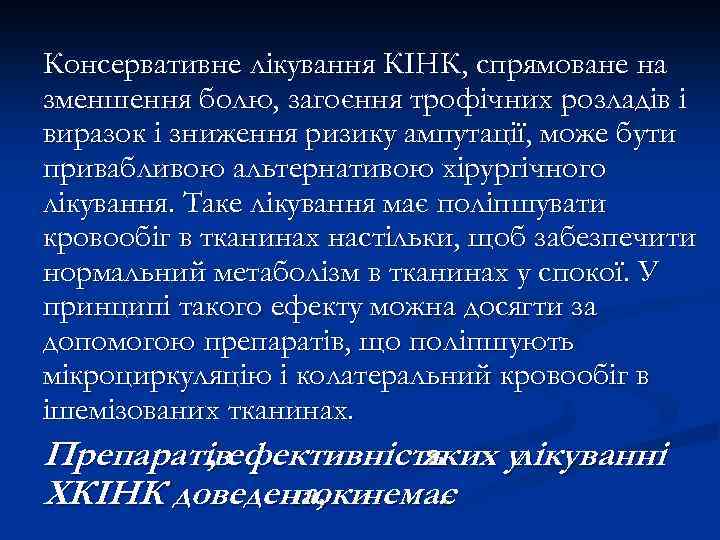

Консервативне лікування КІНК, спрямоване на зменшення болю, загоєння трофічних розладів і виразок і зниження ризику ампутації, може бути привабливою альтернативою хірургічного лікування. Таке лікування має поліпшувати кровообіг в тканинах настільки, щоб забезпечити нормальний метаболізм в тканинах у спокої. У принципі такого ефекту можна досягти за допомогою препаратів, що поліпшують мікроциркуляцію і колатеральний кровообіг в ішемізованих тканинах. Препаратівефективність , яких улікуванні ХКІНК доведена, немає поки.

Консервативне лікування КІНК, спрямоване на зменшення болю, загоєння трофічних розладів і виразок і зниження ризику ампутації, може бути привабливою альтернативою хірургічного лікування. Таке лікування має поліпшувати кровообіг в тканинах настільки, щоб забезпечити нормальний метаболізм в тканинах у спокої. У принципі такого ефекту можна досягти за допомогою препаратів, що поліпшують мікроциркуляцію і колатеральний кровообіг в ішемізованих тканинах. Препаратівефективність , яких улікуванні ХКІНК доведена, немає поки.